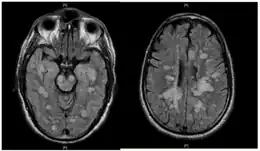

Imagerie

L'IRM cérébrale montre des lésions multifocales de la substance blanche :